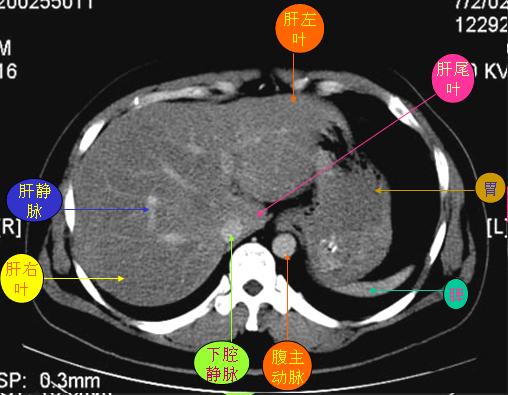

腹部ct解剖与基本病变